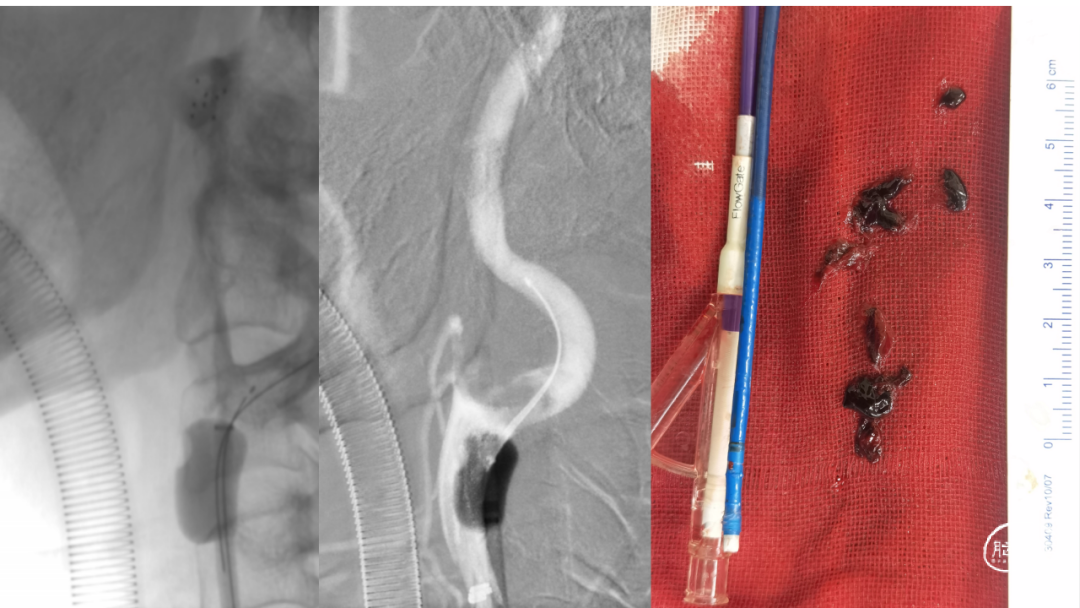

取之有道·第54期|李子付:Flowgate2取栓应用

看李子付解“取之有道”

滑动浏览更多内容